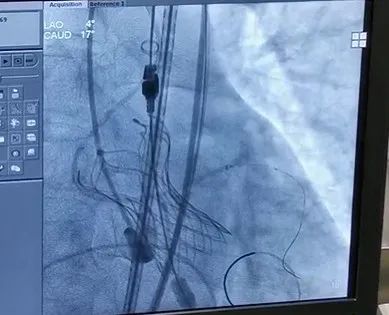

在室速状态下成功释放人工瓣膜

全麻后,成功穿刺右股动脉,通过穿刺点输送系统将瓣膜输送至病变的主动脉瓣处,经过严密地心电监护、心脏食道超声引导,手术团队在心室快速起搏下,使得收缩压降到 60 mmHg、脉压差小于 10 mmHg,此时释放人工生物瓣膜取代自身病变的瓣膜,食道超声检查无瓣周漏,人工瓣膜工作正常,手术完美结束。